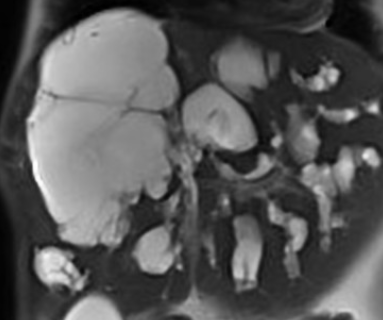

US Neonatal

- type I: most common, accounting for 80-90% (this type can present in utero)